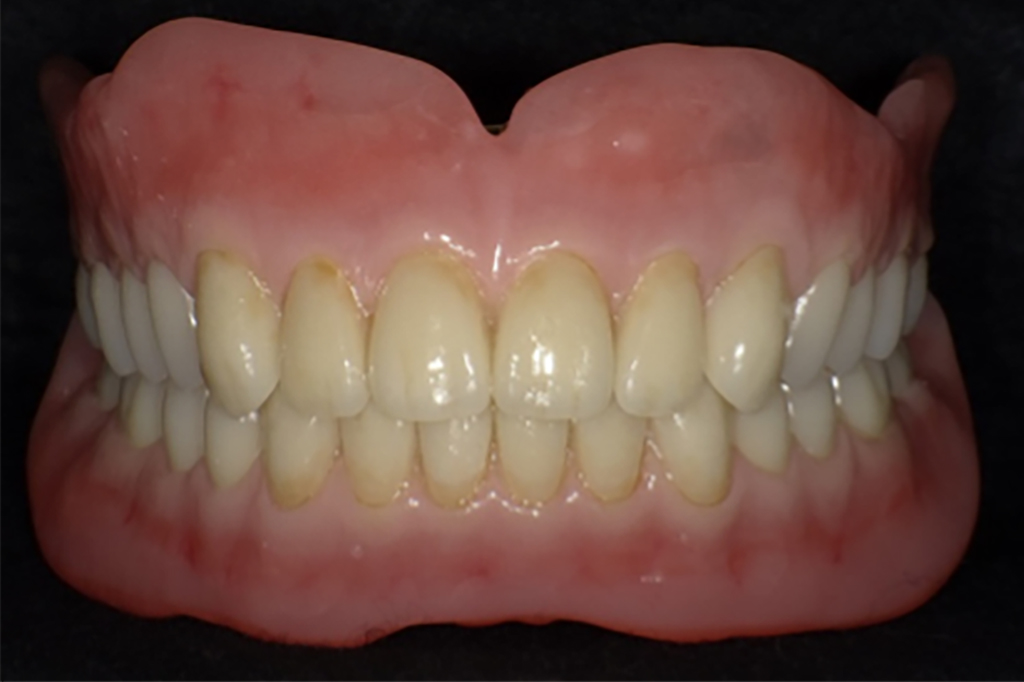

入れ歯(義歯)の完成・調整

兵庫県南あわじ市・医療法人 太田歯科・矯正歯科

入れ歯が完成した後は、実際に使用して調整を行います。

ご自身でもかみ合わせや見た目をご確認いただきながら、入れ歯を快適に使用できるようにしていきます。